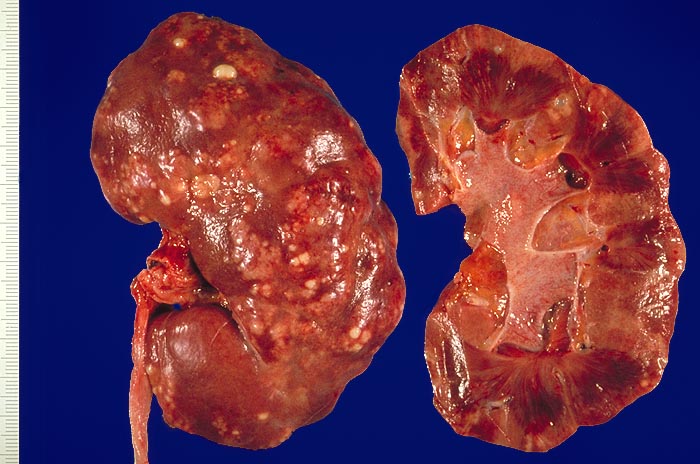

Vorkommen: